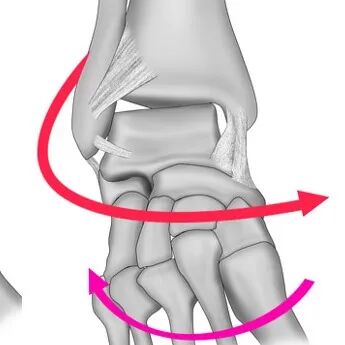

所有的踝关节骨折,损伤均在两个平面内进行:

-

冠状面:旋前外展、旋后内收型;在冠状面上的按次序损伤,形成损伤“冠状环”;冠状环由内踝、三角韧带、距骨、外踝、外侧韧带组成;

轴向面(横断面):旋前外旋、旋后外旋损伤,在轴向面上依次损伤各结构,形成“轴向环”,轴向环由下胫腓前韧带、外踝(外侧韧带)、下胫腓后韧带、内踝组成。